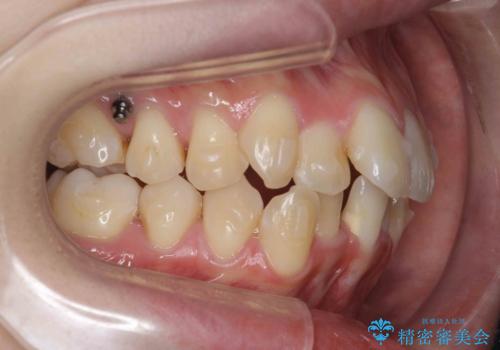

前歯のがたつきをマウスピース矯正できれいに!

- 目立つ前歯のがたつきを改善したい、と矯正治療を希望され来院されました。

今回の治療ではシミュレーションでしっかりと検討した結果、下顎は前歯を1本抜去し仕上げる治療計画としました。